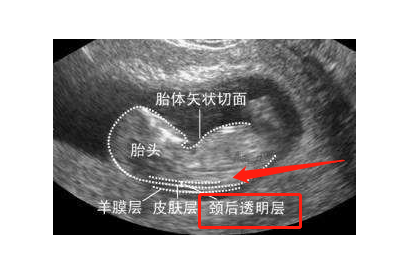

不神秘nt是胎儿脖子后的透明带

nt检查又称颈后透明带扫描,是通过b超来测量胎儿颈后透明带的厚度

nt(nuchal translusancy thickness)即胎儿颈后透明带,指胎儿颈背侧软